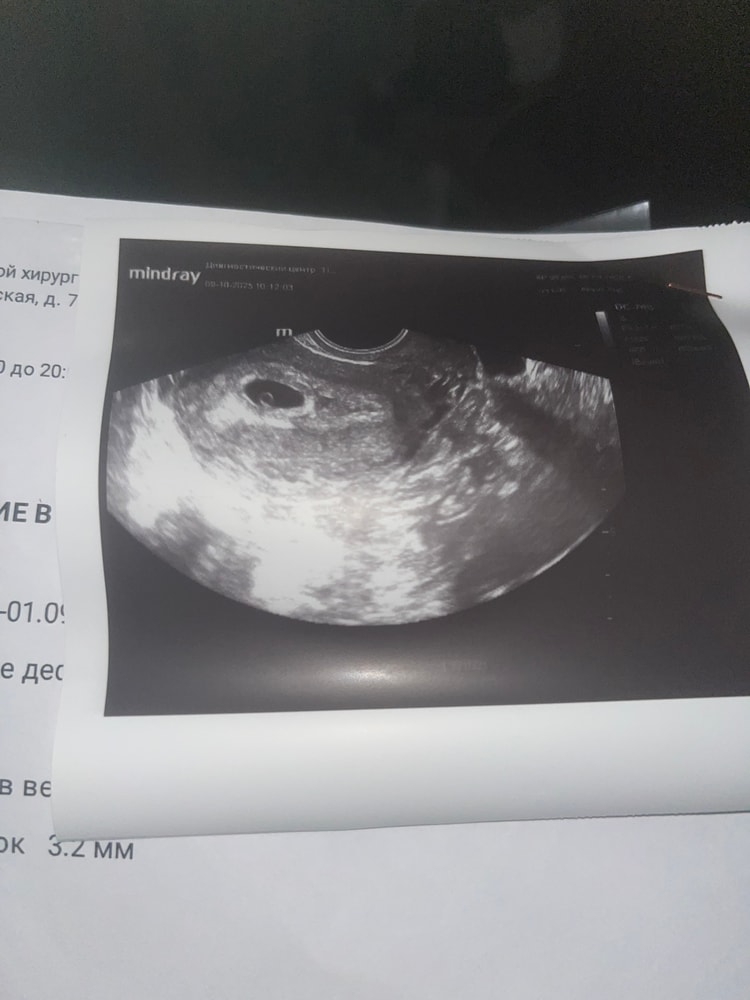

Сегодня 5 недель 4 дня, сходила на узи. Скажите пожалуйста, все ли хорошо ?

Повторное узи 17 числа